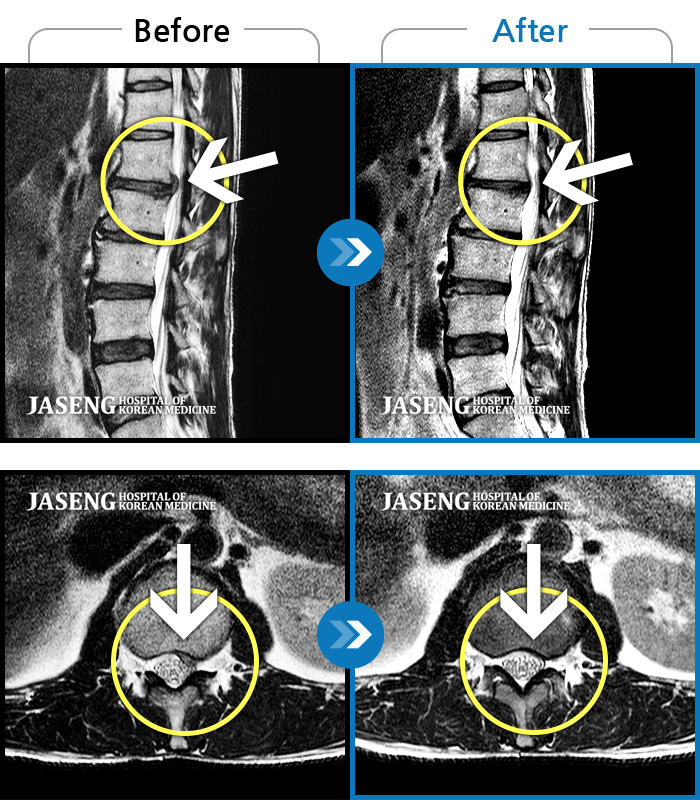

Before

After

환자에게 사전 동의를 받아 동일 조건에서 촬영되었습니다.

개인에 따라 치료 후 부작용이 발생할 수 있으니 의료진과 상담 후 치료를 진행하시기 바랍니다.

우측 허리 통증 및 다리 저림이 심하여 앉거나 바로 눕는 것도 힘든 상태로 내원하셨습니다. 감각 저하도 동반되어 심각한 신경손상이 의심되는 상황이었습니다.

양측 하요추부 통증과 우측 하지부 통증